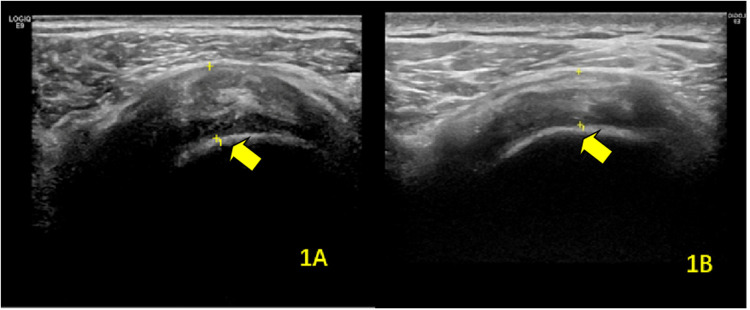

Methods: We conducted a study involving 80 stroke patients with hemiplegia and concomitant shoulder pain on the affected side, admitted to our hospital between April 2020 and March 2021. MSUS was used to evaluate shoulder structures, including the long head of the biceps brachii tendon (BICT) and its sheath, rotator cuff, subacromial-subdeltoid (SA-SD) bursa, labrum, acromioclavicular ligament, acromiocoracoid ligament, and acromion-greater tuberosity (AGT) distance. We compared pre- and post-rehabilitation measurements of supraspinatus tendon (SST) thickness, BICT sheath effusion thickness, SA-SD bursa effusion thickness, AGT distance, and visual analog scale (VAS) scores. Statistical significance was set at P < 0.05.

Results: Post-rehabilitation, the SST thickness on the hemiplegic side showed a statistically significant reduction (P = 0.023). No significant difference was observed in the mean maximum rupture diameter (P = 0.796). Both BICT sheath effusion (P < 0.001) and SA-SD bursa effusion (P < 0.001) exhibited significant decreases. The AGT distance on the hemiplegic side also demonstrated a statistically significant change (P < 0.001). Additionally, the VAS score significantly improved post-rehabilitation (P < 0.001).

Abstract Image